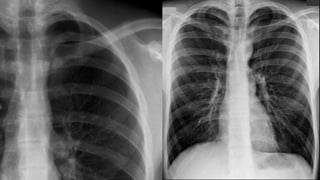

The characteristics of

pneumothorax

◦ Pleural line

◦ No lung markings in

The outer margin of

visceral pleura separated

from the parietal pleura

by a lucent gas space

devoid of pulmonary

vessels

in erect position

in supine position

Air in apicolateral pleural space Air in anteromedial pleural space.

Erect

Small

Apical lucency

Visceral

pleural line

Large

(>2cm in width)

Tension

Lung collapse

Mediastinal shift

Low flat

diaphragm